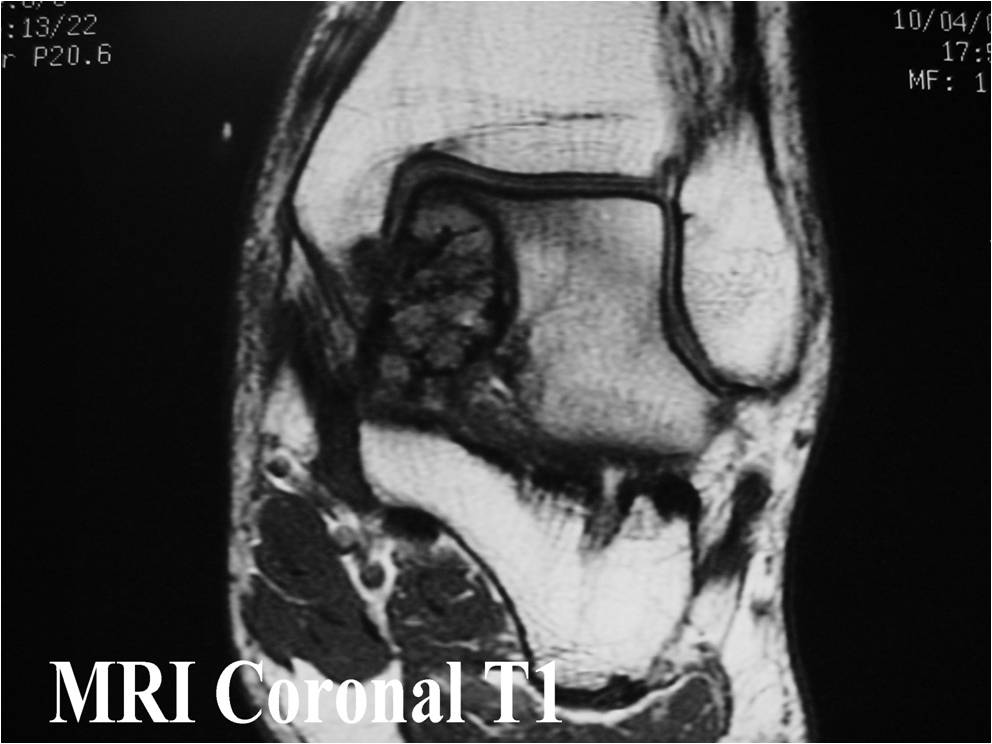

- (MRI appearance)

- Geographic, well circumscribed lesion in the epiphysis

- Intermediate Signal on T1

- High signal on T2 mixed with low signal areas (low signal areas proposed to be secondary to lysosomal content of highly cellular areas)

- Fluid/Fluid levels demonstrated in tumors that have undergone ABC change (aneurysmal bone cyst change)

- Extensive Surrounding edema is common

- Joint effusion in 30-50% of cases